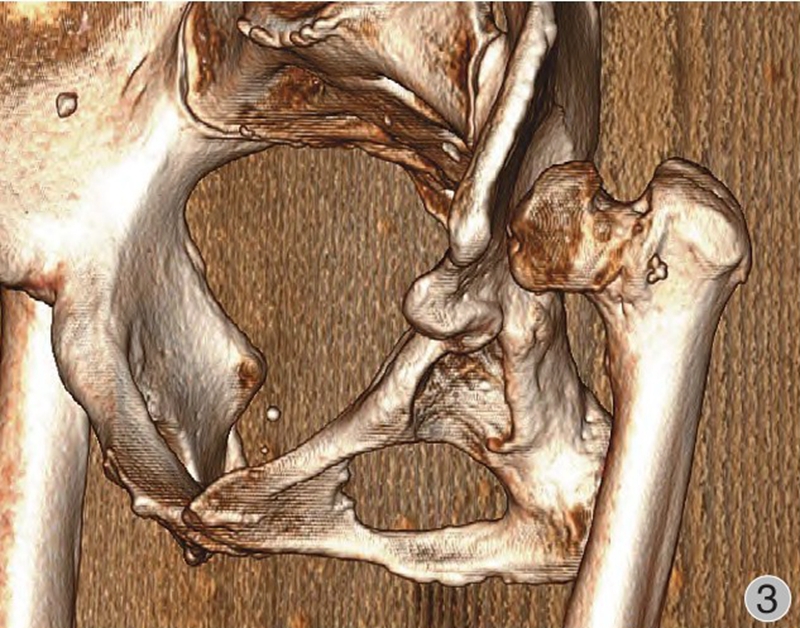

由于股骨头半脱位或脱位,发育中的真性髋臼缺乏应力刺激未能正常生长发育,骨性髋臼形成通常较小,多呈三角形,被软组织所覆盖,部分病例会有骨性覆盖以及骨性解剖标志丧失等(图1~3)。发育不良的髋臼往往较浅且前倾增大,前壁变薄,骨量不足,前后径减小,可有上方和(或)前方节段性缺损。根据是否存在假臼,有学者将Crowe Ⅳ型进一步分为Ⅳa(无假臼)和Ⅳb(有假臼),并提出假臼的存在是影响THA脱位高度和转子下截骨术应用的重要因素,HARTO等发现无假臼的高脱位DDH患者THA术后假体存留率不及有假臼形成患者,并且假臼的存在与否影响近端股骨的应力传导并可能与近端股骨形态有关,因此包含形态分类的术前规划是有必要的。如何寻找真臼的位置以及髋臼杯的安放是手术成功的关键。

图3 术前髋关节CT三维重建(左侧观):股骨头脱位高度>股骨头高度的100%。真臼未能正常发育,髋臼浅小呈三角形,前倾增大,前后柱骨质丰厚,无大量骨缺损;左侧股骨头小,股骨颈短,颈干角、偏心距减小,股骨头与髂骨翼未形成假臼;股骨近端骨皮质变薄,髓腔窄小变直,呈柱状